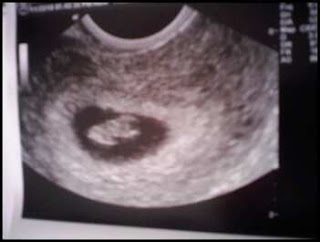

After the pelvic exam, I had a quick vaginal u/s and got to see the heart beat. They also said I'm measuring right on schedule of my LMP. Due date 7/9/11

Here's my souvenior of the day...

.. but it was exciting to see the little heart beating and get some peace of mind.

Im late, as always but SO excited for you Erinn! I love the lil u/s pic! So cute.